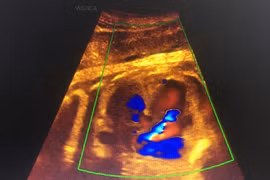

(khoahocdoisong.vn) - Các dải xơ buồng ối quấn thắt vào thai nhi không chỉ gây khoèo chân, cụt chi, tổn thương não, nội tạng và dị tật cho các bộ phận khác mà còn gây sẩy thai, thai lưu. Để cắt dải cơ buồng ối, Bệnh viện Phụ sản Hà Nội là đơn vị công lập đầu tiên trong cả nước thực hiện thành công phẫu thuật nội soi bằng laser quang đông bào thai trong bụng mẹ.

(khoahocdoisong.vn) - Khi mắc hội chứng truyền máu song thai nếu không được điều trị thì 90 - 100% thai sẽ chết. Còn nếu một trong hai thai chết thì 25% thai còn lại bị di chứng thần kinh nặng nề. Bệnh viện Phụ sản Hà Nội là bệnh viện đầu tiên trong cả nước thực hiện được kỹ thuật.

(khoahocdoisong.vn) - Siêu âm còn là phương pháp bắt buộc trong theo dõi sản khoa, giúp bà mẹ thêm an tâm về sự phát triển toàn diện của con trước khi chào đời.

(khoahocdoisong.vn) - Nhờ kỹ thuật hiện đại, bệnh viện Phụ sản Hà Nội đã phát hiện và theo dõi được một trường hợp có huyết khối xoang tĩnh mạch màng cứng ở thai nhi 29 tuần tuổi.